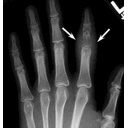

tuberculose osseuse.png